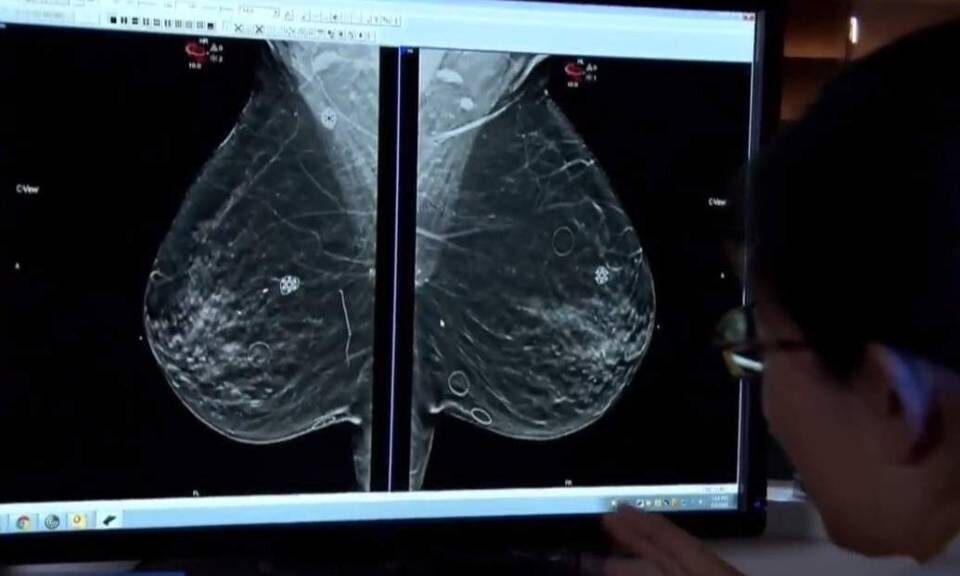

Em outubro, mês da campanha 'Outubro Rosa' de conscientização sobre o câncer de mama, o Espírito Santo comemora a ampliação do acesso à mamografia, que agora estará disponível para todas as mulheres a partir dos 40 anos.

Em outubro, a Prefeitura de Aracruz, por meio da Secretaria de Saúde, intensifica ações de prevenção ao câncer de mama e colo do útero. As Unidades Básicas de Saúde estão com horário estendido para orientar sobre mamografias e exames preventivos, visando informar e conscientizar mulheres de todas as idades.

A Assembleia Legislativa (Ales) promoveu, na manhã de quinta-feira (10), uma ação em apoio ao Outubro Rosa, com alunos de Enfermagem do Instituto Humboldt orientando servidoras e visitantes sobre prevenção ao câncer de mama e colo do útero, sob a supervisão da enfermeira Michelle Rocha.

Outubro é o mês do "Outubro Rosa", uma campanha global da OMS para conscientização sobre o câncer de mama. A Secretaria da Saúde destaca a importância do cuidado com a saúde da mulher, enfatizando a prevenção e a detecção precoce da doença, que afeta milhões de mulheres no Brasil e no mundo.